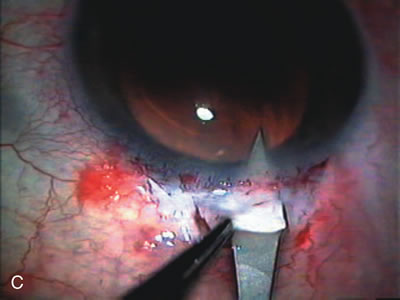

Fig. 7. Phacotrabeculectomy adjacent to a failed filter in cataractous eye. The ability to combine small-incision cataract extraction with trabeculectomy all through the same incision adjacent to the failed filter allows the surgeon to work in a familiar superior area. Avoiding incisions into the existing bleb decreases conjunctival buttonholes, hypotony, operating room time, and subconjunctival bleeding. A. Appearance of failed bleb with exposure of superior temporal quadrant gained with a corneal traction suture. B. Prepare a limbus-based conjunctival flap and a scleral flap. C. This bleb is at high risk to fail again justifying the need for MMC, 0.2 mg/cc applied on a pledget for 4 minutes. D. Insert the keratome and perform phacotrabeculectomy in the usual fashion.